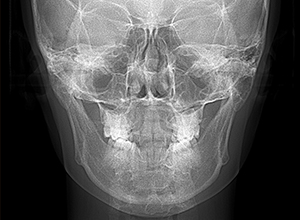

| X-Ray所見 | |

| セファロ所見 | 下顎枝、骨体部共に大きくしっかりとしており、バランスの良い形をしていた。上顎突出度は大きく、ANB6.0°と前後的にはⅡ級を呈していた。 |

| パノラマ所見 | 上顎両側第三大臼歯は存在して挺出が認められた。 |